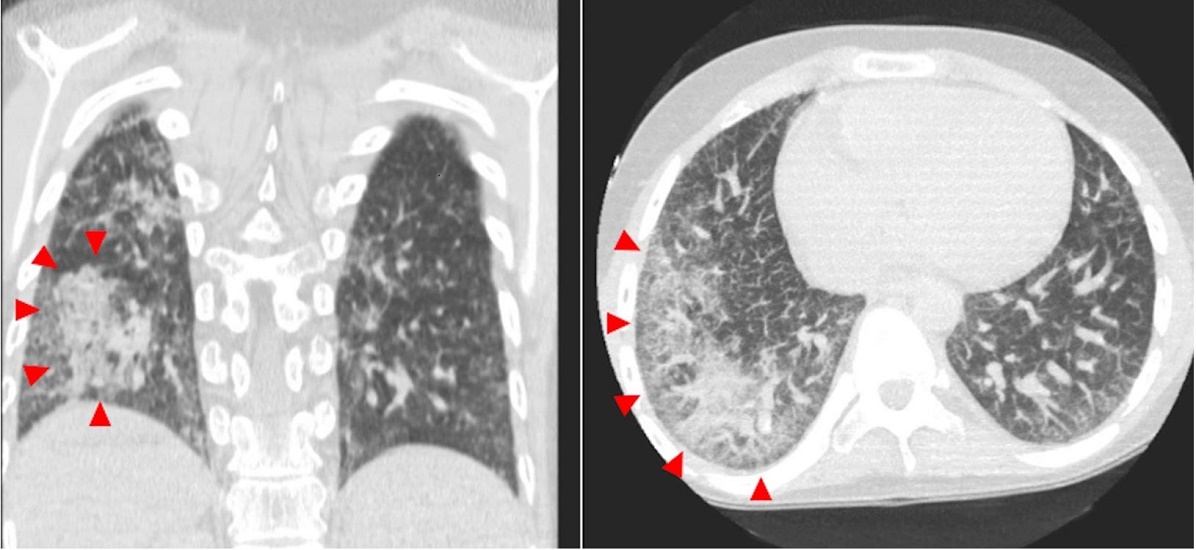

A 16-year-old boy with a known medical history of DC due to TINF2 mutation was admitted to the pediatric intensive care unit due to worsening respiratory distress and hypoxia. Since the diagnosis, his clinical course was complicated by bone marrow failure status post-transplant with persistent pancytopenia, nodular regenerative hyperplasia of the liver, hypersplenism with portal hypertension, chronic gastrointestinal bleeding due to small vascular malformations of the intestine requiring constant blood transfusions, and restrictive lung disease. The recent onset of respiratory distress was related to the development of hepatopulmonary syndrome. The physical examination disclosed a thin, ill-appearing, tachypneic (44/min), and tachycardic (153 bpm) adolescent in moderate respiratory distress with a high fever (38.5 C) and decreased breath sound in the right lower lung fields. Generalized dry and mottled appearing skin with prominent veins and pallor was present. No abdominal distension or tenderness, or edema were observed. A CT scan of the chest showed extensive reticulation, interlobular septal thickening, signs of pulmonary hypertension, and patchy confluent areas of perihilar and peripheral airspace disease, mainly on the right lung (Figure 1).

On internal examination, both lungs showed multiple areas of consolidation, mainly in the right lung (Figure 3). Postmortem lung cultures were collected in the attempt to detect potential etiologic agents, but no viral or bacterial organisms were isolated. Histology of lung samples showed diffuse alveolar damage with acute and organizing pneumonia in addition to thickened pulmonary arteries consistent with pulmonary hypertension. The lower lobe of the right lung showed more prominent fibrosis with increased dilated vascular channels. (Figure 4).

Another relevant abnormality that was observed in our case was the extensive pulmonary fibrosis. The lung showed multiple areas of consolidation, and prominent fibrosis with increased dilated vascular channels was found at the histology, likely representing healed areas of prior insults. The lung is commonly involved in a patient with DC, with lung fibrosis being one of the most common pathologic findings. Lung fibrosis has also been associated with mutations of the TINF2 gene. The mechanism that leads to lung fibrosis is still not completely understood. One theory is that the potential shortening of telomeres in the alveolar epithelial cells can lead to an aberrant lung repair process by their premature and enhanced apoptosis, causing pulmonary fibrosis.18,19